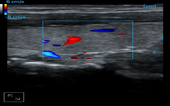

Radial Artery + CF

Thyroid + CF

Thyroid + CF